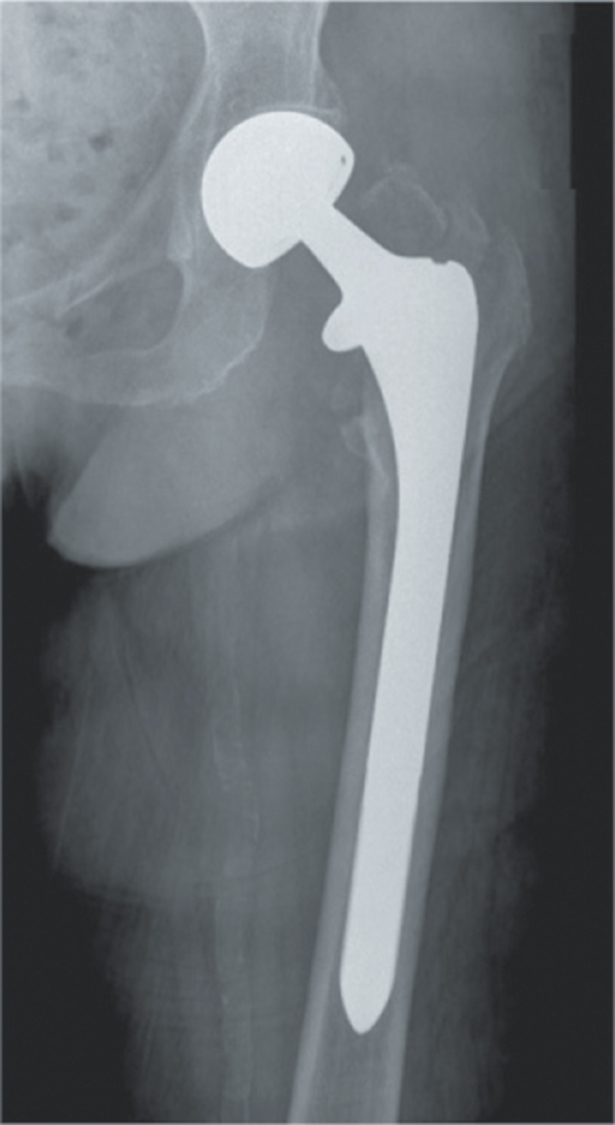

Methods: In this retrospective study, a total of 314 patients who were operated on for hip fractures were included study. Patients were then divided into four groups based in their implant types: long-stem cementless bipolar hemiarthroplasty (n = 124; 102 female, 22 male; mean age = 84.2 ± 6.4 years), standard-stem cementless bipolar hemiarthroplasty (n = 74; 48 female, 26 male; mean age = 83.5 ± 6.9 years), antegrade intertrochanteric nail (n = 61; 35 female, 26 male; mean age = 78.5 ± 6.8 years), and total hip arthroplasty (n = 55; 34 female, 21 male; mean age = 72.5 ± 4.3 years). Data including gender, age, duration from injury to surgery, American Society of Anesthesiologists (ASA) score, comorbidities, use of antiplatelet agents, Barthel Index of Activities of Daily Living, type of anesthesia, operation time, preoperative hemoglobin values, blood transfusions given, duration of hospital stay, complications, and type of fracture were recorded.

Abstract Image